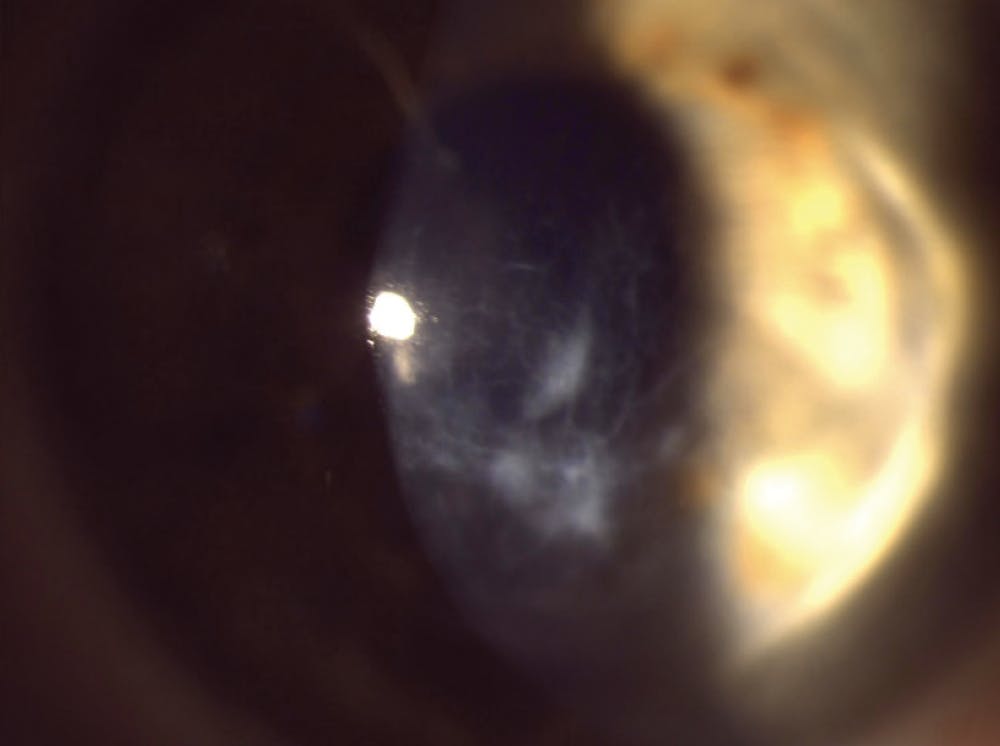

Practitioners who don’t fit scleral lenses may not be aware of the tremendous advances that have been made in this category, as well as with other specialty lenses in the past 10 years. They are no longer a “long shot” or a “modality of last resort.” Although scleral lenses don’t treat keratoconus per se (ie, they don’t halt the disease process), we can almost always help a patient see better with a specialty lens fit no matter what stage keratoconus they have. In fact, there are many cases where even a patient with late-stage keratoconus who might be considered a candidate for corneal transplantation may be able to postpone or prevent the need for a transplant with just a new scleral lens fit (Figure 2).

Furthermore, imaging can help resolve doubts—or provide a much-needed baseline against which to measure future change. In fact, if your hunch turns out to be correct and the patient does have keratoconus (Figure 1), the sooner you obtain baseline imaging the better, as it may be needed to show disease progression. If the imaging comes back normal, you have done your job and fully evaluated the patient. I have yet to hear a patient complain about me being “too thorough.”